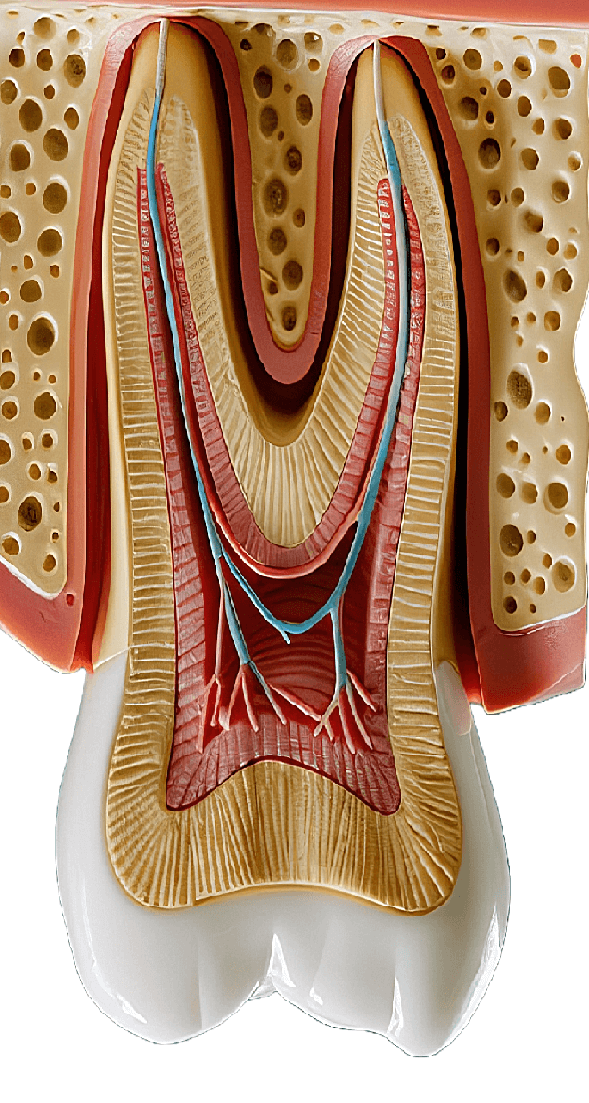

Procedure involving removal of infected pulp tissue, disinfection, and sealing of the tooth to manage infection and preserve function.